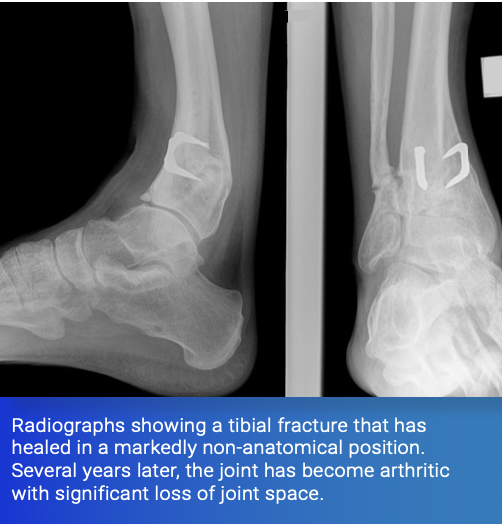

5) Mal-Alignment of a Joint Due to Distant Fracture

The forces passing through a joint are balanced to equalise pressure on the cartilage. If a fracture heals in a non-anatomical position, this can alter the delicate balance, resulting in early arthritis of the joint. For this reason, great care is given, when stabilising long bone fractures, to ensure correct alignment is restored.